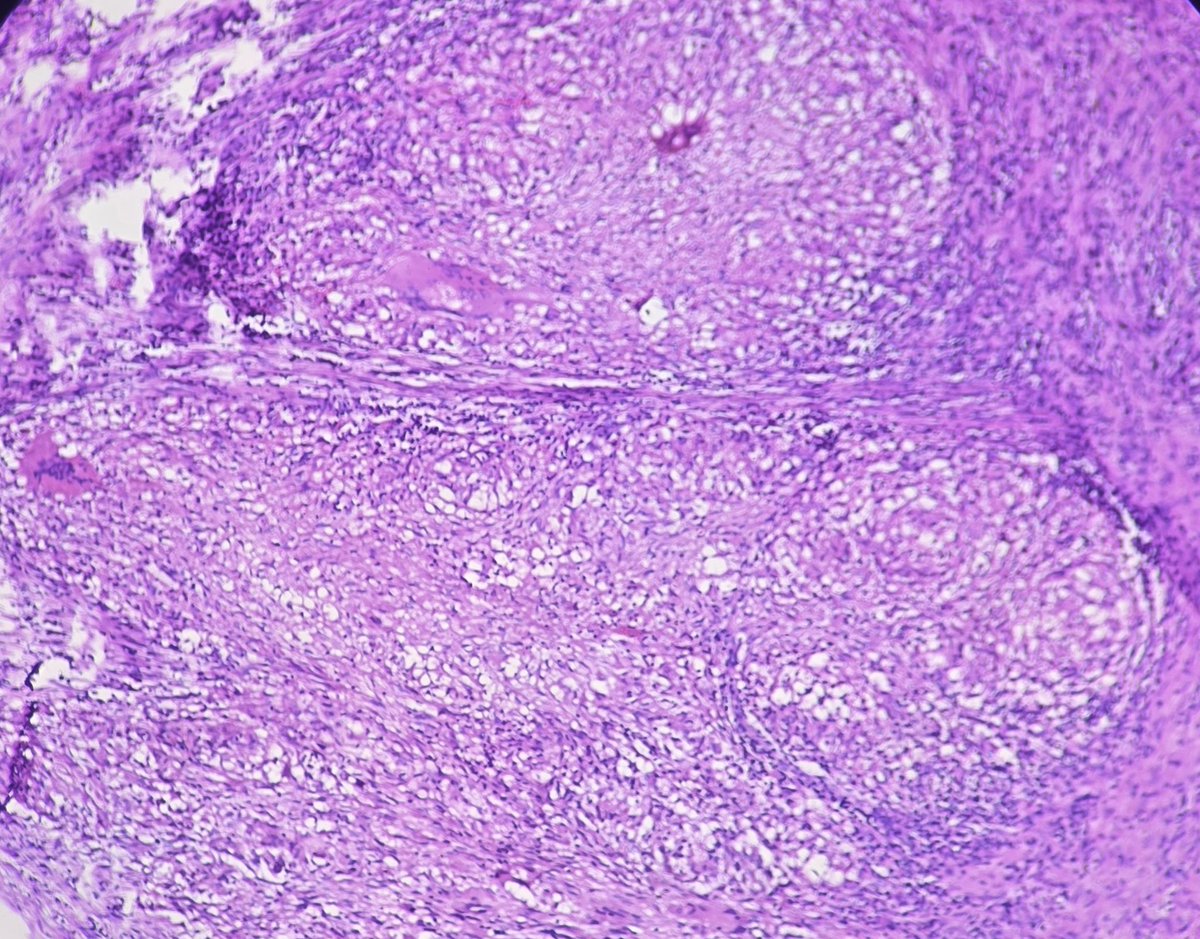

Papillary squamous cell carcinoma of cervix is a rare variant of squamous cell carcinoma of the cervix characterized by papillary architecture with fibrovascular cores and malignant squamous epithelial lining.

#pathology #gynepath #SCC #Papillary